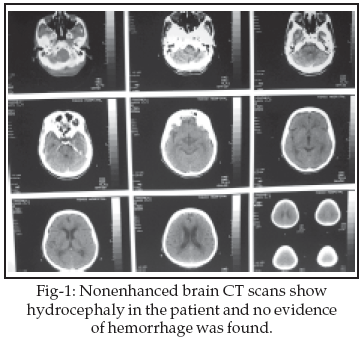

Although neurological symptoms in brucellosis are frequent, central nervous system (CNS) involvement is uncommon. A 42-year-old man was admitted with an episode of faint without loss of consciousness, right hemi paresis, diplopia and headache lasting for four days. The neurological examination revealed left hemi paresis. Limitation of gazing in left eye in lateral view was seen (partial paresis of 6th cranial nerve). The results of laboratory examinations show positive Wright and Coombs Wright in blood and C.S.F. In the brain CT scan hydrocephaly and in magnetic resonance imaging (MRI) some brain atrophy, few high signal foci in the deep with mater had been detected. Treatment included concurrent administration of three drugs: doxycycline, rifampicin and co-trimoxazole. This patient fully recovered.

In the primary brain CT no lesion was seen but some days later hydrocephaly has been detected. In brain magnetic resonance imaging (MRI), some brain atrophy and few high signal foci in the deep white matters of both brain hemisphere was reported. There was not any S.O.L in the supra and infra tentorial structures.